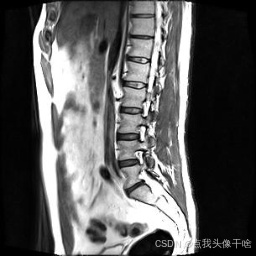

想象一下,你给AI看一张脊椎的核磁共振(MRI)照片,它就能像经验丰富的医生一样,把照片里每一块骨头、每一节椎间盘都给你清清楚楚地标记出来。这个系统干的就是这个酷炫的事儿!

- 原图:就是一张张脊椎的MRI扫描图。